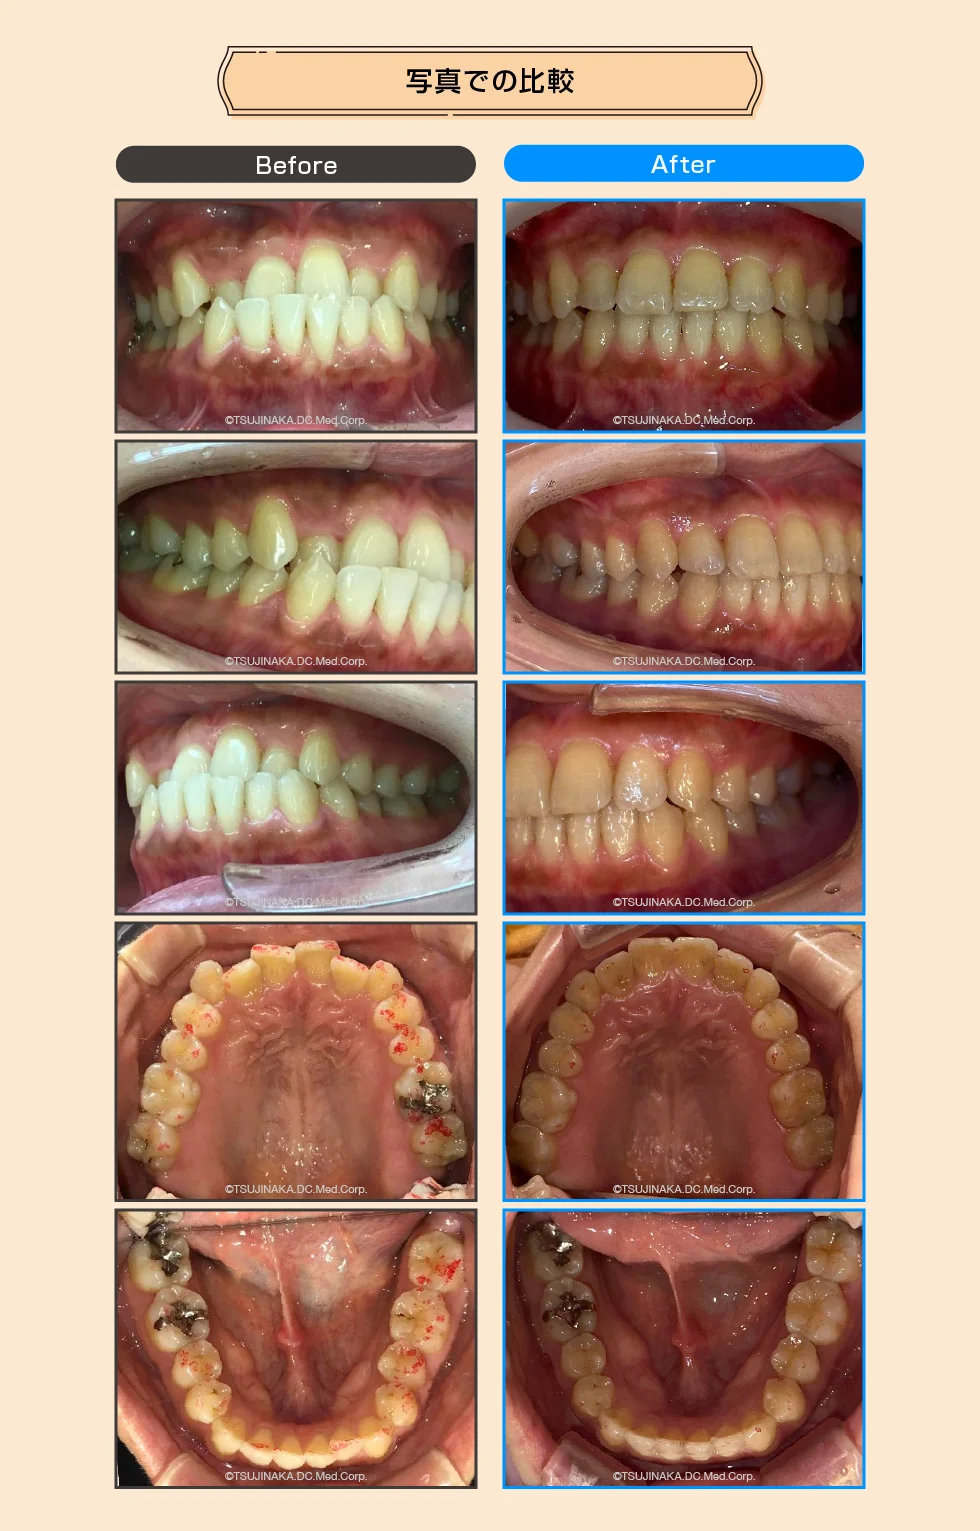

この患者さんは反対咬合と叢生歯列だけでは無く、患者さんの気づいてられなかった点として咬合が強く、下顎隆起という噛み合わせが強い人の特徴があった。 治療計画として早期に前歯部の反対咬合を治す必要があった。 反対咬合→叢生歯列→咬合回復 アフターの写真の右下の奥歯(写真左側)を見て貰えると、右下567の3本の歯が真っ直ぐに起き上がって咬み合わせも治っています。

| 主な症状 | 1.(受け口)反対咬合 2.(上下前歯デコボコ)叢生歯列 |

| 治療期間・回数 | 1年6ヶ月、14回 |

| リスク・副作用など | 反対咬合だったのでゴム掛けが必要だったので、モチベーション維持が大変とIPRが必要 |

| ドクターから一言 | 初診時39歳だったので早期に反対咬合を治す為に下顎前歯部にIPRを慎重に行なった。又、顎自体を引っ込める力をかける時に顎関節を痛めない様に注意深く観察、指導した。 |